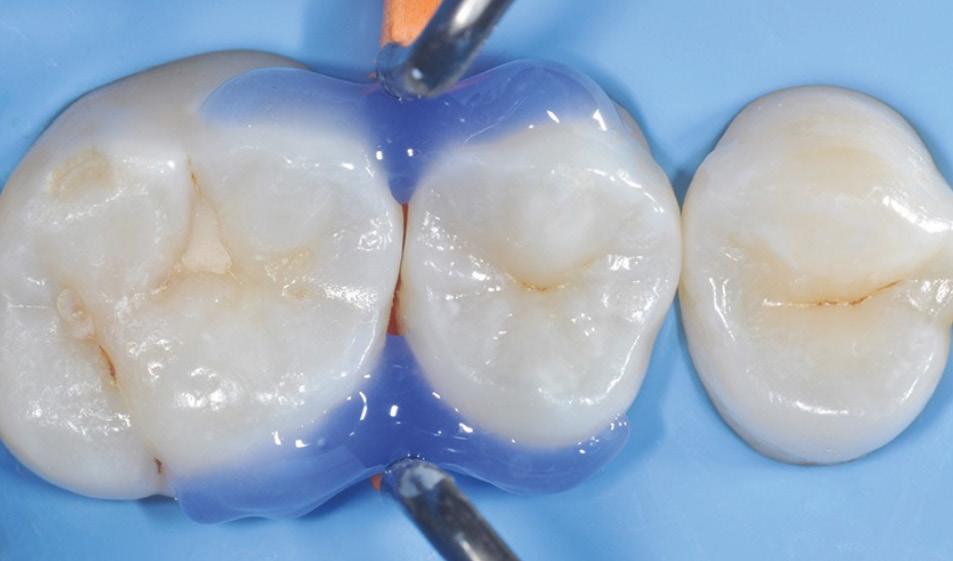

Fig. 5: Caries removal and cavity preparation. Caries detection dye was used as a Fig. 6: A 15 second selective enamel etch using 3M™ Scotchbond™ Universal Etchant followed by rinsing and air drying. Fig. 7: 3M™ Scotchbond™ Universal Adhesive was scrubbed into the preparation for 20 seconds followed by air-drying and light-curing with 3M™ Elipar™ LED Curing Light for 10 seconds.* Fig. 8: 3M™ Filtek™ One Bulk Fill Restorative A3 was placed in one increment. The composite was cured for 10 seconds on the occlusal surface.*